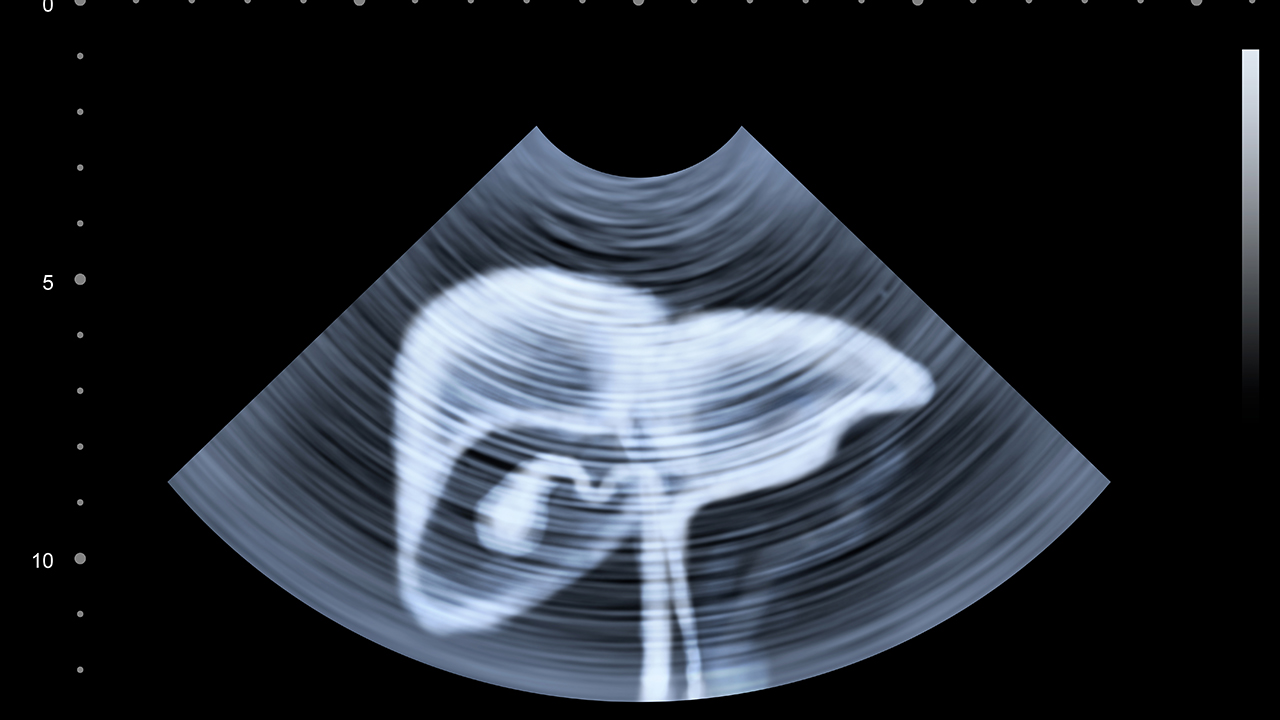

肝癌是一种常见的恶性肿瘤,其发病原因复杂,包括病毒性肝炎、肝硬化、长期酗酒、黄曲霉毒素暴露等。早期肝癌症状不明显,容易被忽视,因此定期体检对于高危人群尤为重要。肝癌的治疗方法包括手术切除、肝移植、射频消融、介入治疗、靶向治疗和免疫治疗等,具体方案需根据患者的病情和身体状况制定。

肝癌的预防与健康管理对于降低发病风险和提高治果至关重要。高危人群,如慢性乙肝、丙肝患者、长期酗酒者、有肝癌家族史的人群,应定期进行肝脏超声和甲胎蛋白检查,以便早期发现病变。日常生活中应避免饮酒、吸烟,保持健康饮食,减少高脂肪、高糖食物的摄入,多吃新鲜蔬菜和水果。同时,保持良好的作息习惯,避免过度劳累,适当进行体育锻炼,增强免疫力。对于已经确诊的肝癌患者,应积极配合医生的治疗方案,定期复查,保持良好的心态,有助于提高治果和生活质量。